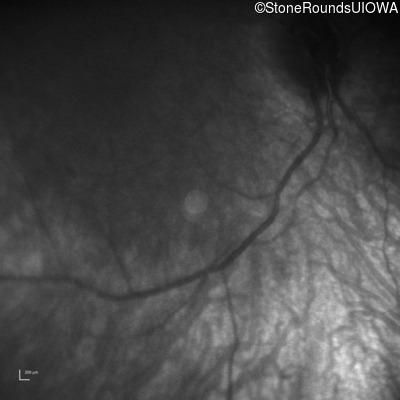

Infrared Fundus Photograph - Right -

No Light Perception

Exemplar

Expanded OCT Stack

×